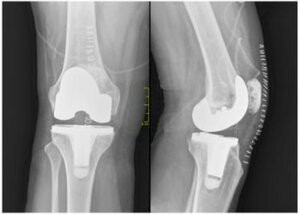

Robotic Knee Replacement surgery